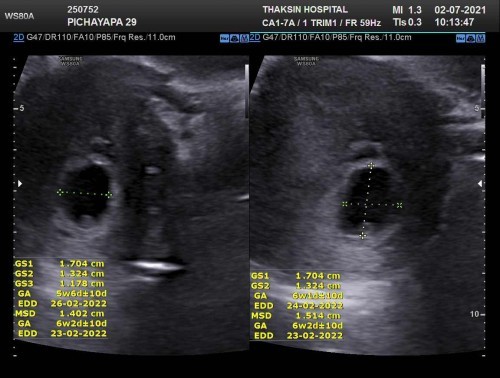

9 week ไปซาวด์ครั้งแรก เจอแต่ถุงตั้งครรภ์ และไข่แดง หมอบอก อายุครรภ์ ในภาพซาว์ แค่ 5 weekหมอนัดซาวด์ทางช่องคลอดอีก 2 อาทิตย์ ข้างหน้า ตอนนี้เครียดมากคะ กลัวไม่เจอตัวน้อง แม่ๆท่านใดมีประสบการณ์ แบบนี่ ขอคำแนะนำหน่อยนะคะ

ตอนนี้ คุณหมอบอกท้องลมคะ 10 วีคแล้วไม่เจอน้อง แต่คุณหมอยังให้โอกาสอีก 2 อาทิต ตอนนี้คือเครียดจิตตก แอบร้องไห้ตลอดเลยคะ มีใครเคยเจแหลังจากนี้ไหม ตอนนี้แม่ทำใจแล้วคะ ซาวผ่านช่องคลอด นะคะ คุณหมอว่า แม่นสุดแล้ว เสียใจมากเลย แต่อีก 2 อาทิต ปม่ก็ขอหวังไว้ก่อน